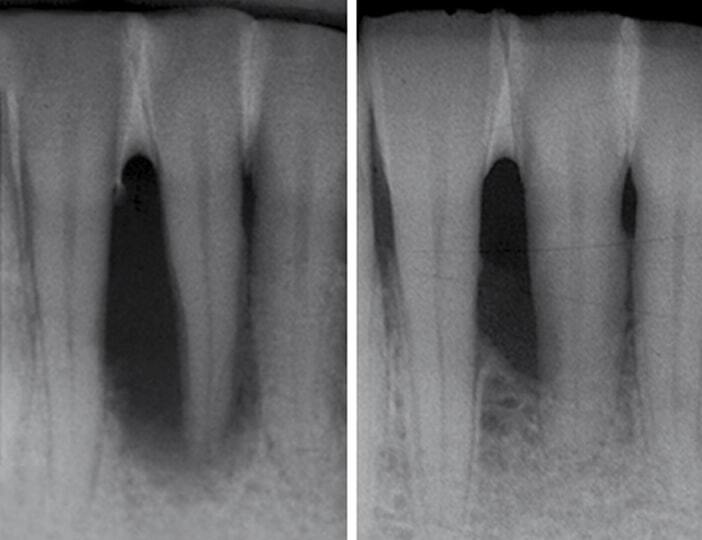

Пациент обратился с жалобой на подвижность зуба

2025-04-29 08:21